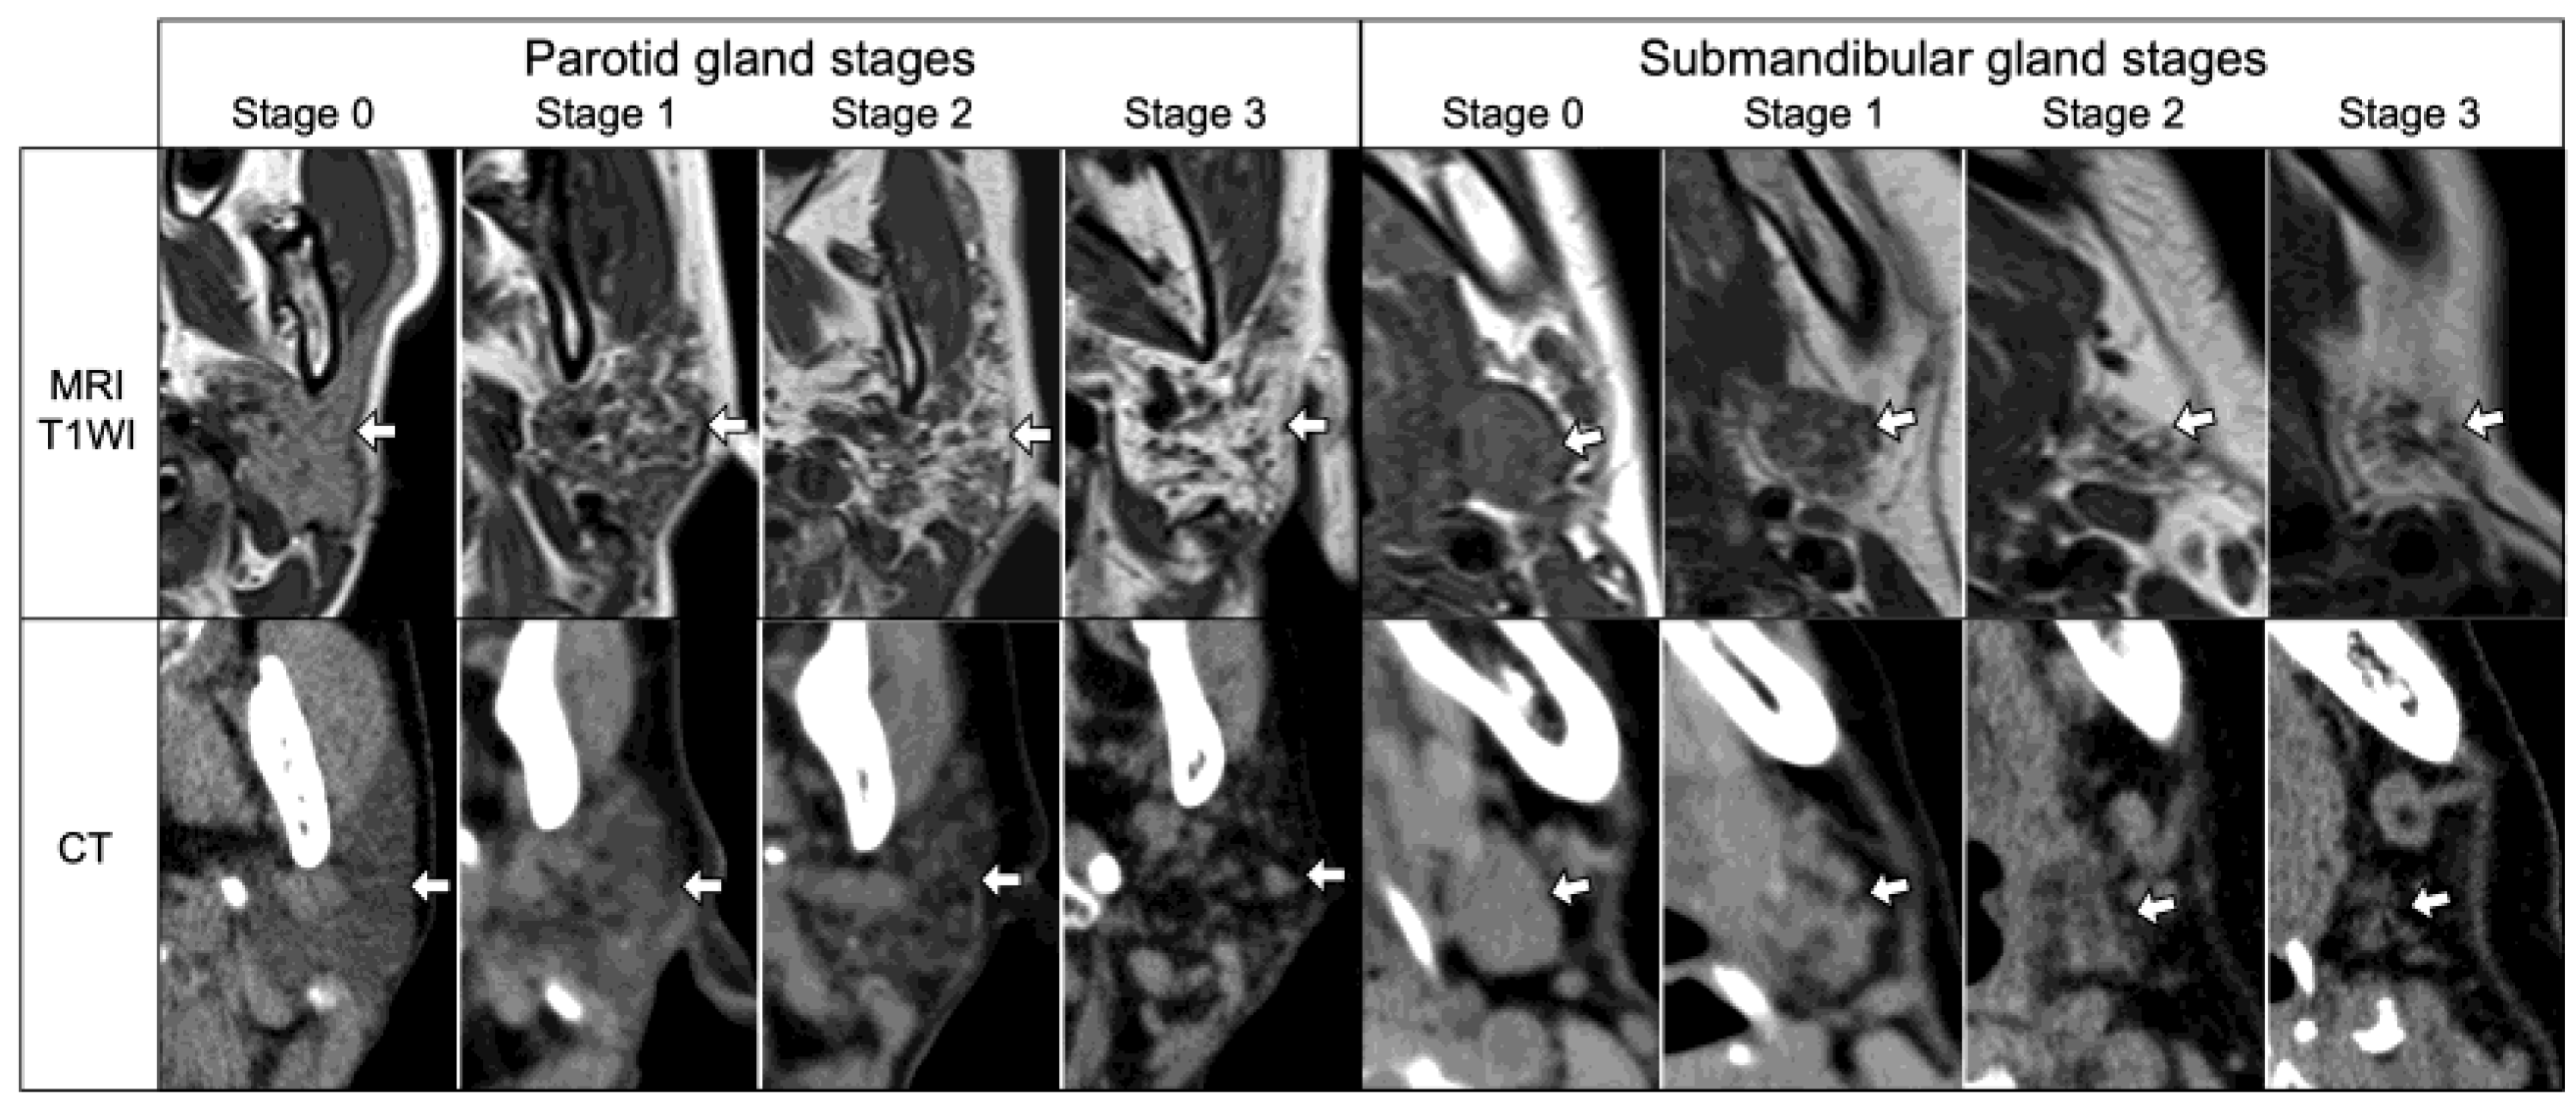

2.5. Salivary Gland SS Disease Stage Score